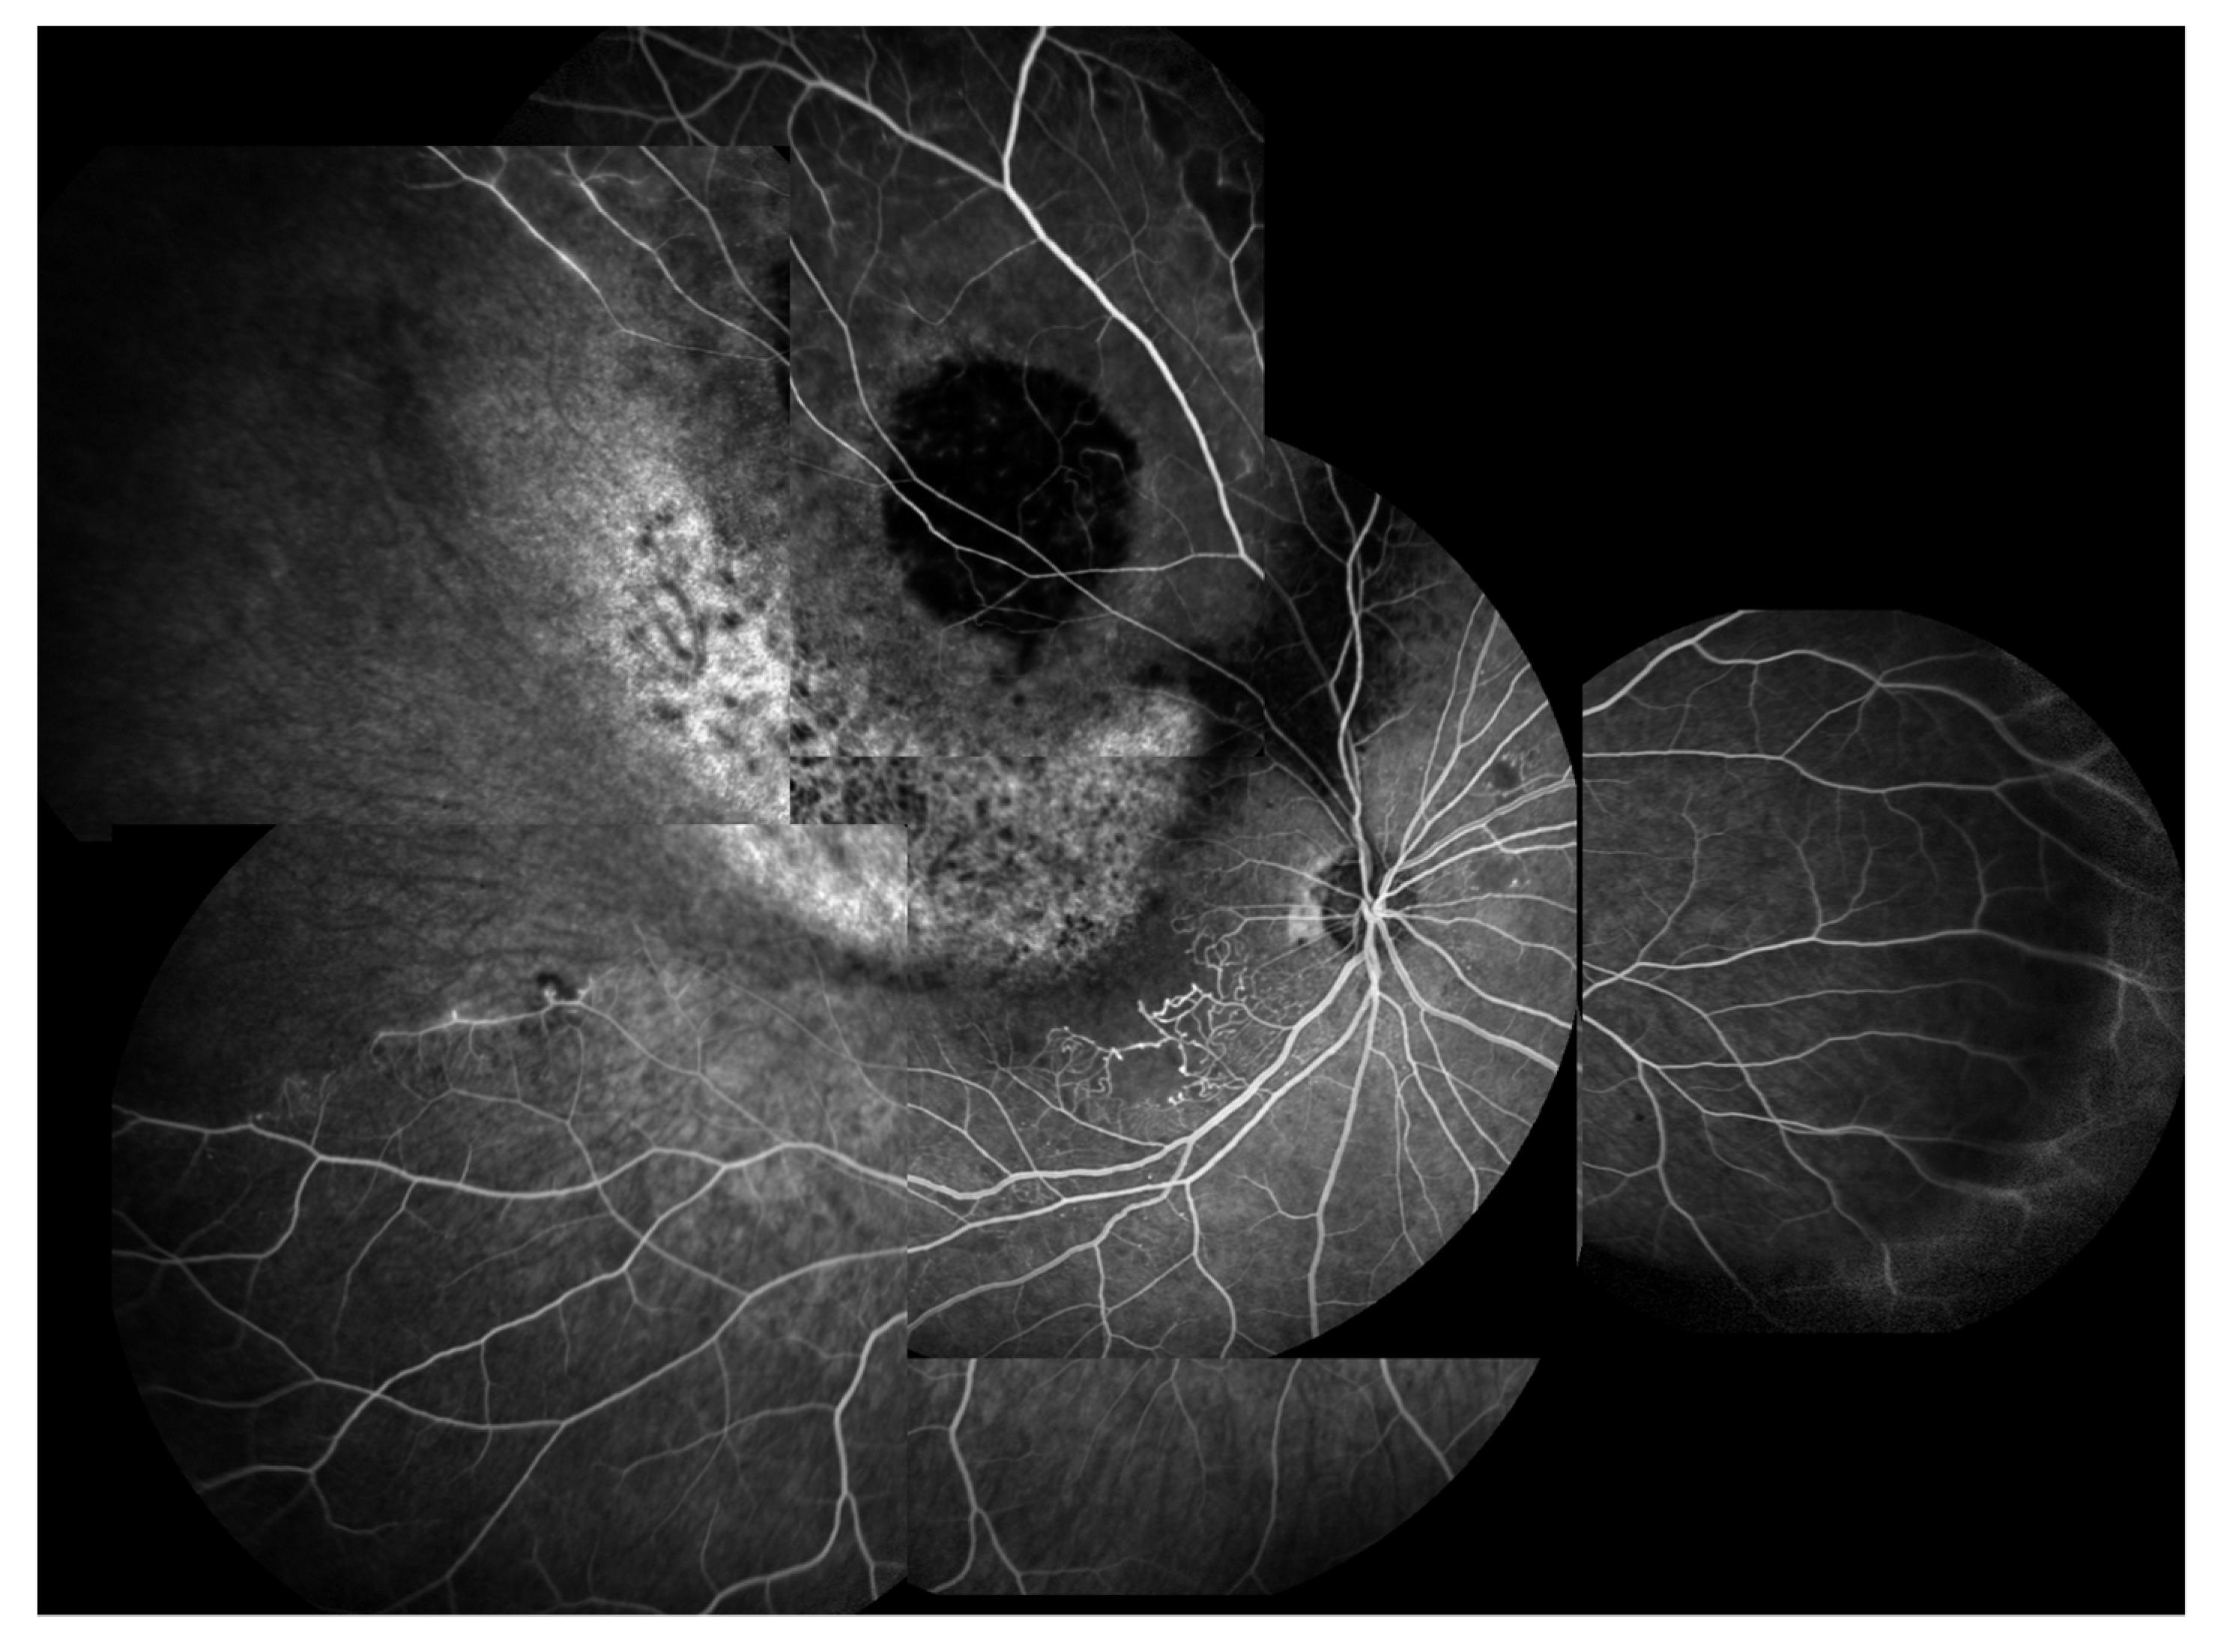

3.1. Radiation (Chorio)Retinopathy